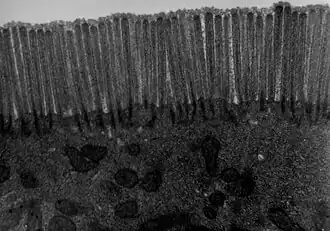

Microscopía electrónica del yeyuno -

ME del yeyuno de un ratón x14000